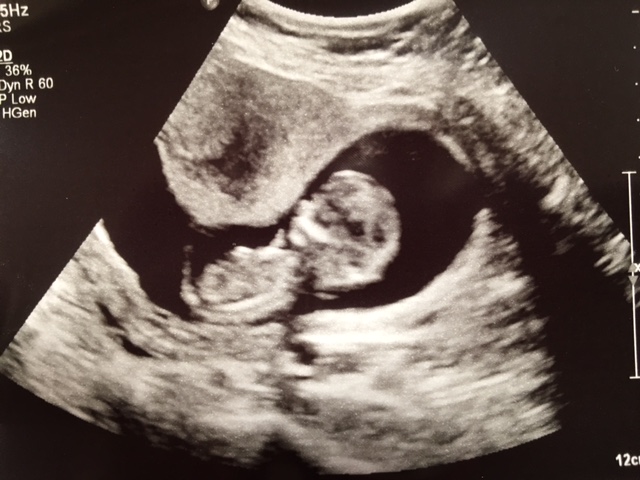

abdominal. Attachment 32903

All the other pics cut the body off before the lower area. Im so bummed this is the best shot!